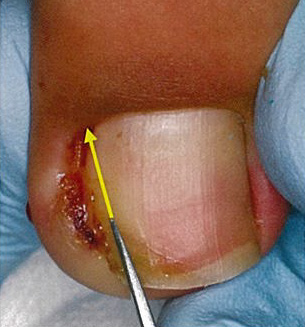

重症や難治性の方が対象です。皮膚に食い込んでいる爪甲側縁を必要最小限に切除し、刺さった状態を解除してあげることが大事です。局所麻酔を併用し、爪甲側縁を楔状に切除し、肉芽形成を伴う場合には肉芽も切除してしまいます。局所麻酔の痛みと出血がありますが、治療後は悩みの種であった痛みは数日内で治まり、皮膚の炎症は速やかに収束に向かいます。この方法では基本的に爪母が温存されることから、後遺症を残す可能性はほとんどありません。

②局所麻酔の注入

③爪甲側縁の切除